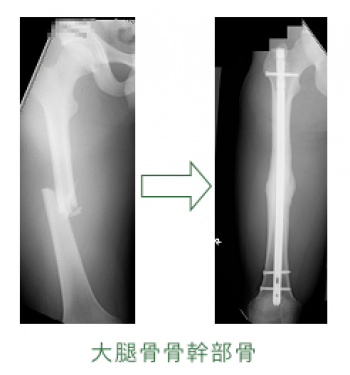

今日、ご紹介するのは、大腿骨骨幹部骨折についてご紹介していきます。

大腿骨骨幹部骨折

大腿骨骨幹部骨折は、比較的頻度が高い。

20〜50歳の青壮年に多発するが小児もまれではない。

骨幹部骨折は常に強力な外力により発生するため軟部組織損傷も高度で、開放性骨折になりやすい。